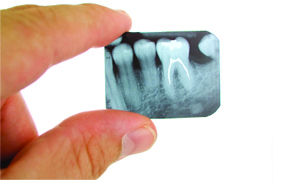

Endodontia